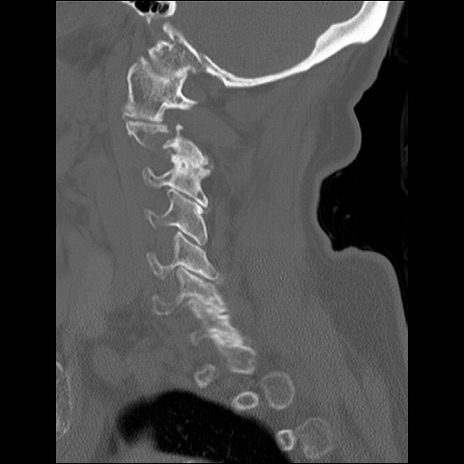

症例48 頚椎CT(矢状断像)

頚椎CT